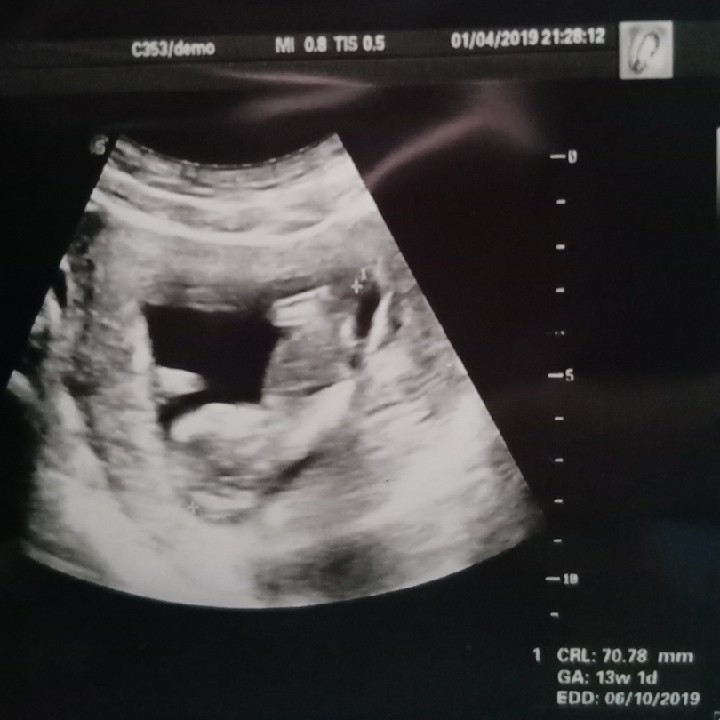

13wค่ะ ตอนนี้22wแล้ว